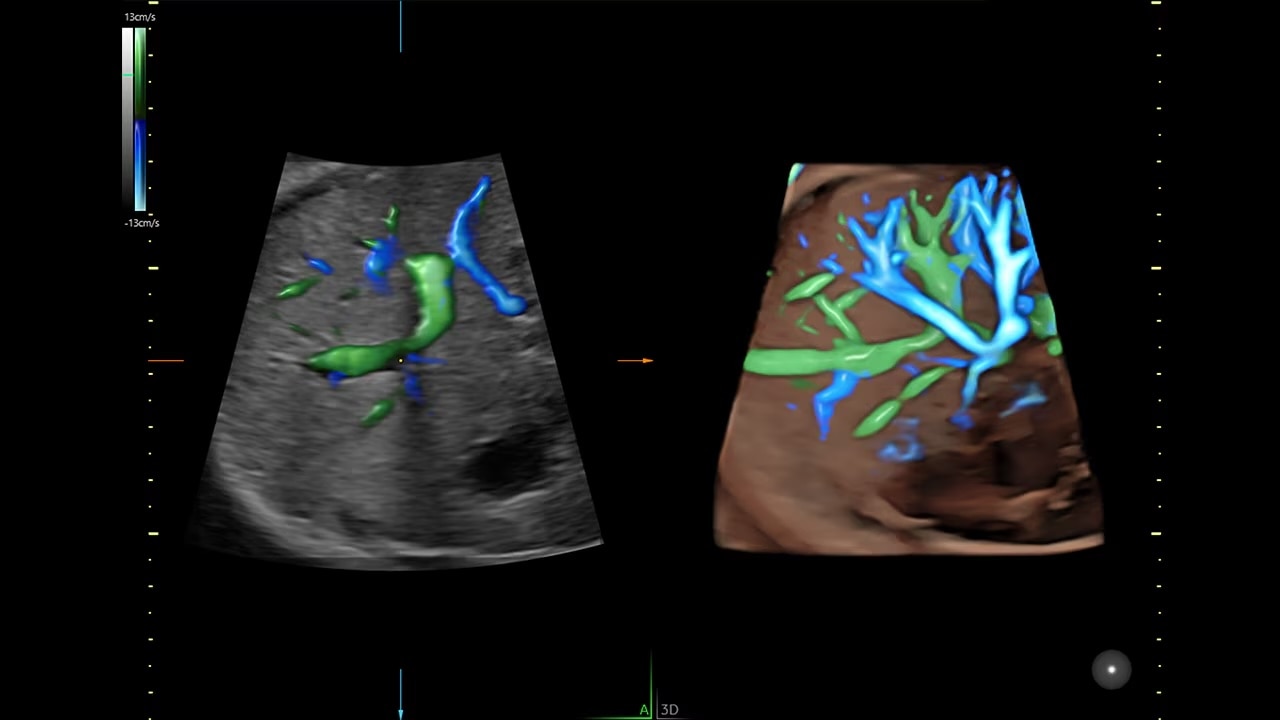

Next level color Doppler that delivers exceptional sensitivity for easy, fast visualization of blood flow, displaying a 3D like appearance as seen in this 27-week fetal heart.